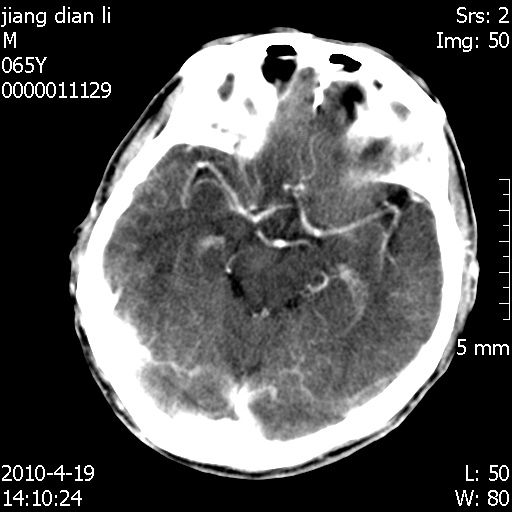

今天上班后发现病人前天复查(4月18日发病,19日初诊,22日复查),三个病灶均明显增大,边缘仍旧清楚,水肿加重,右侧脑室基本闭塞。

我想:如果是肿瘤出血的话,一般不会导致体积明显改变,水肿又进一步加重;如果是出血灶,那么现在应该正好是水肿加重的时候,还是比较符合,但是为什么边缘又是这样的特点?

今天遇到临床医生,询问病人情况,病人已经死亡。

最后看到的病人右侧瞳孔呈针尖大小,估计是继发脑干梗死,而非脑疝死亡。

遗憾! 复习了复查片:发现顶叶出血灶破入侧脑室,侧脑室体部见少许高密度。